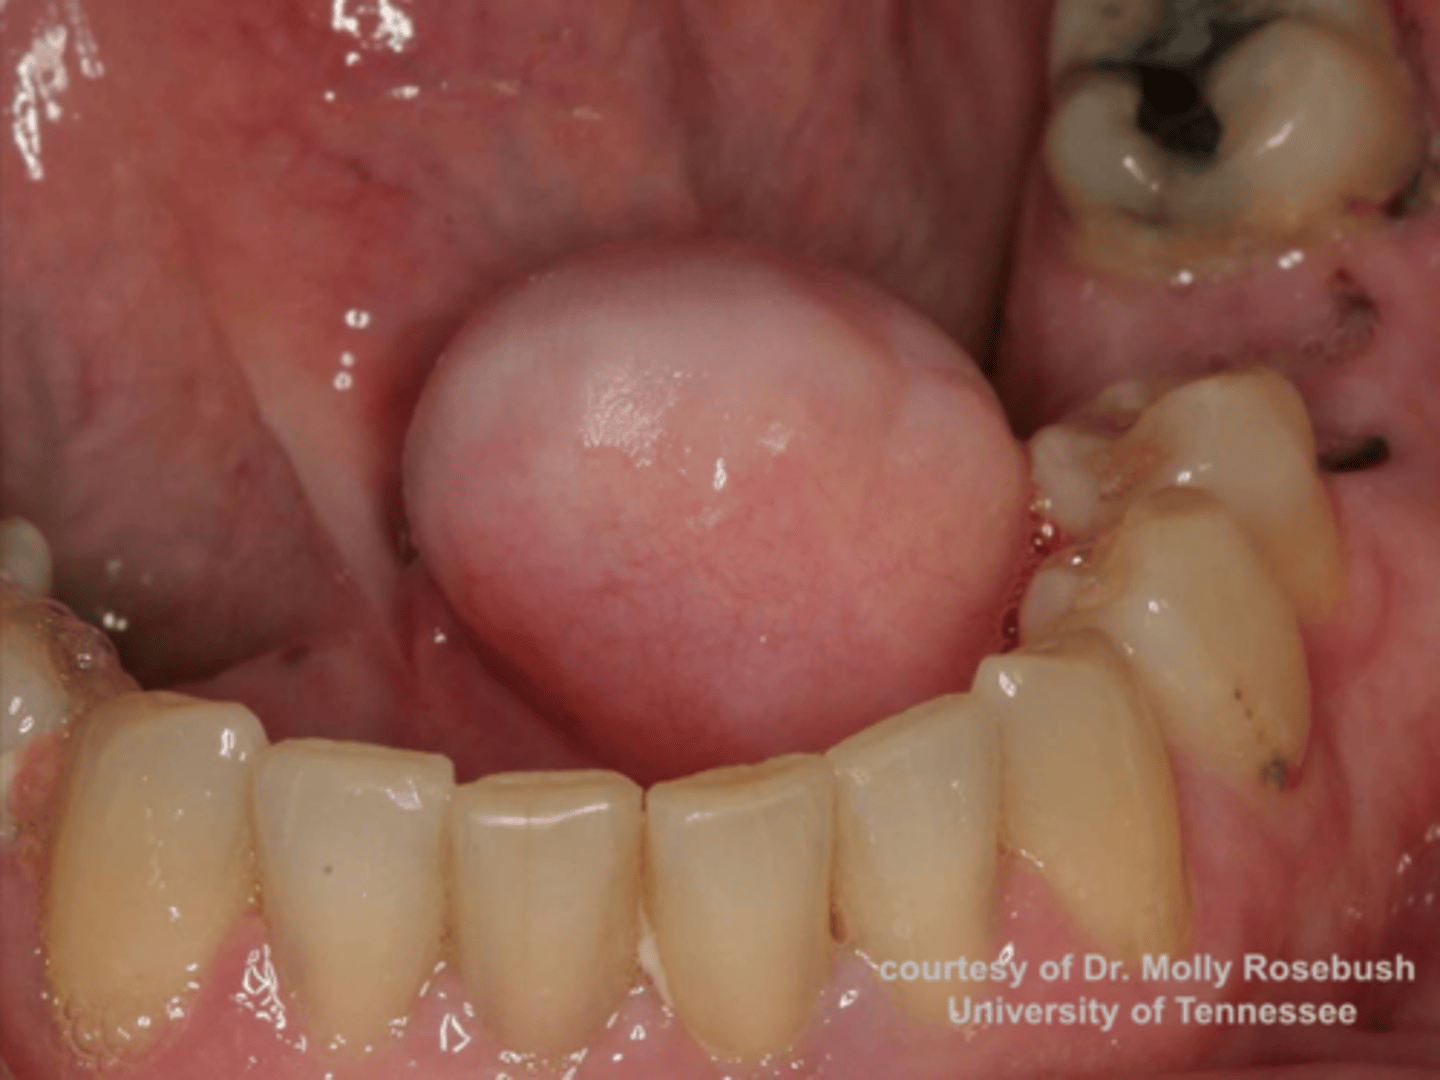

Congenital Epulis

3 week old female patient presents with a nodular formation on the maxillary gingiva lateral to the midline. Histopathology showed cells with granular cytoplasm resemble granular cell tumors. NO pseudoepitheliomatous hyperplasia were present. What do you suspect?

Congenital Epulis

granular cytoplasm with NO pseudoepitheliomatous hyperplasia is associated with what pathology?

Congenital Epulis

-Rare non-neural soft tissue tumor occurring on alveolar ridge of newborns:

Congenital Epulis

This oral pathology resembles granular cell tumor microscopically:

female

Congenital Epulis as a 90% predilection for what gender?

Surgical excision or

Complete regression over time

treatment for Congenital Epulis?